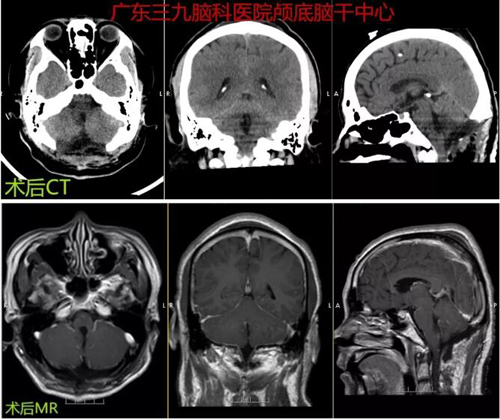

图3:术后CT示四脑室区占位性病变切除术后改变,原病灶已切除。术后MR示四脑室区占位性病变切除术后改变,原病灶已切除